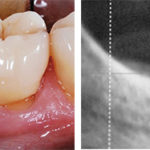

Riabilitazione implantoprotesica nella mandibola posteriore con contestuale rigenerazione ossea verticale mediante osso autologo: caso clinico